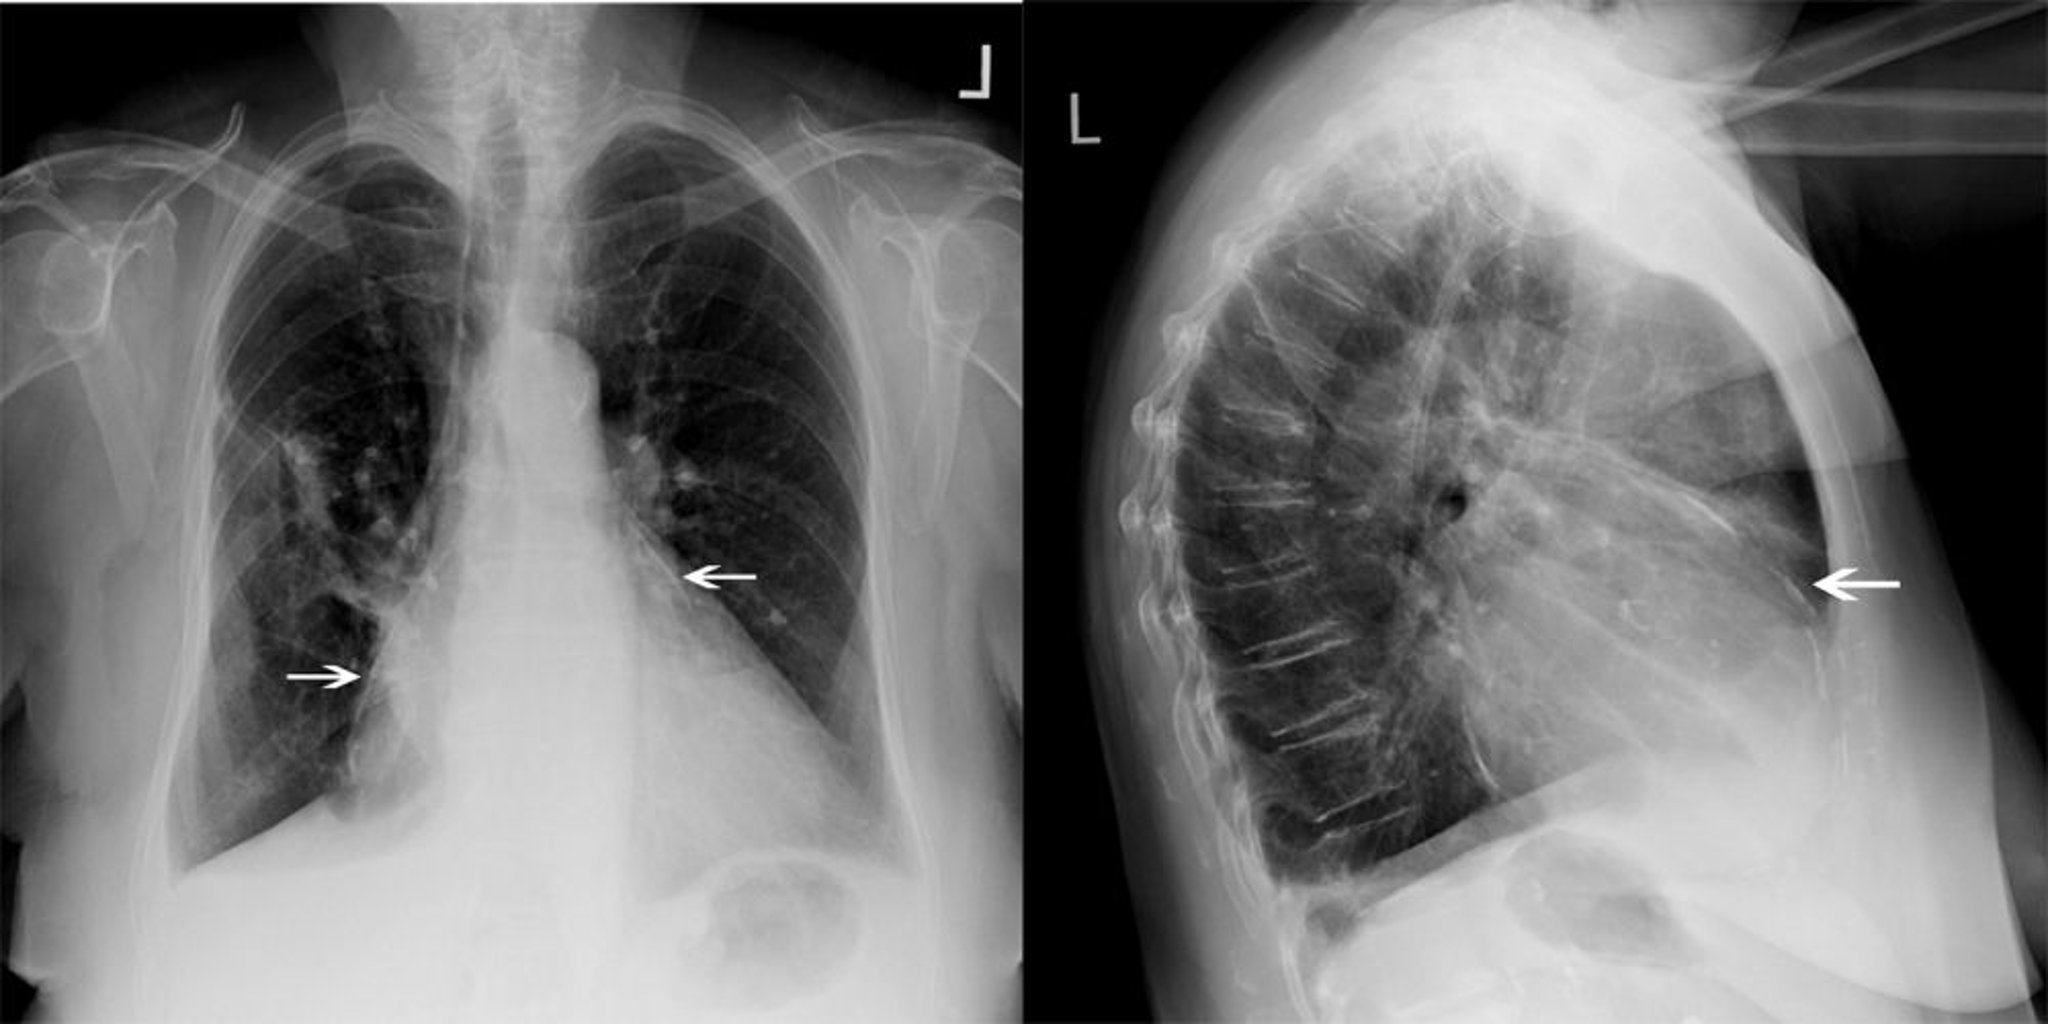

Radiolografia del torace di un paziente con pericardite costrittiva

Questo paziente con pericardite costrittiva ha una calcificazione pericardica significativa (frecce bianche).